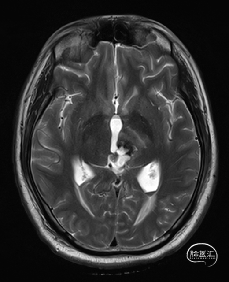

术前MRI检查

术前MRI检查提示左侧丘脑中脑海绵状血管瘤并卒中,梗阻性脑积水;

诊断:1.左侧丘脑中脑海绵状血管瘤并卒中,2.梗阻性脑积水;

年轻患者,较短时间内发生左侧丘脑二次出血,出现右侧面部及上肢麻木,复视,第二次出血后并发梗阻性脑积水,出现头痛。结合病史、神经系统体征、头颅CT及MRI检查,诊断左侧丘脑及中脑CM并卒中、脑积水明确,并导致了神经功能障碍,具备手术指征。

本例患者磁共振检查清晰显示病变位于左侧丘脑中脑区域,且位于丘脑内下方向中脑顶盖延续,病变的上部、前部、外侧部都有重要的神经组织,因此,手术从上方、前方、外侧方向切除病变均难以实施;